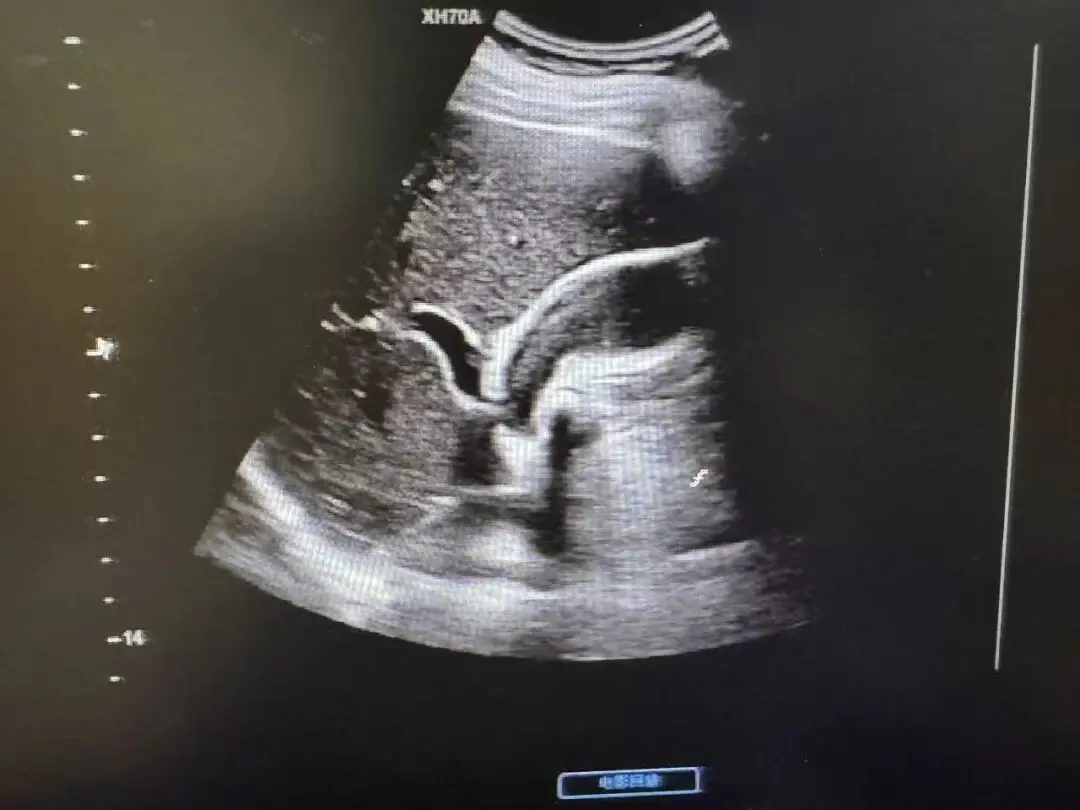

胆囊腺肌症

增厚胆囊壁并其内小液性暗区